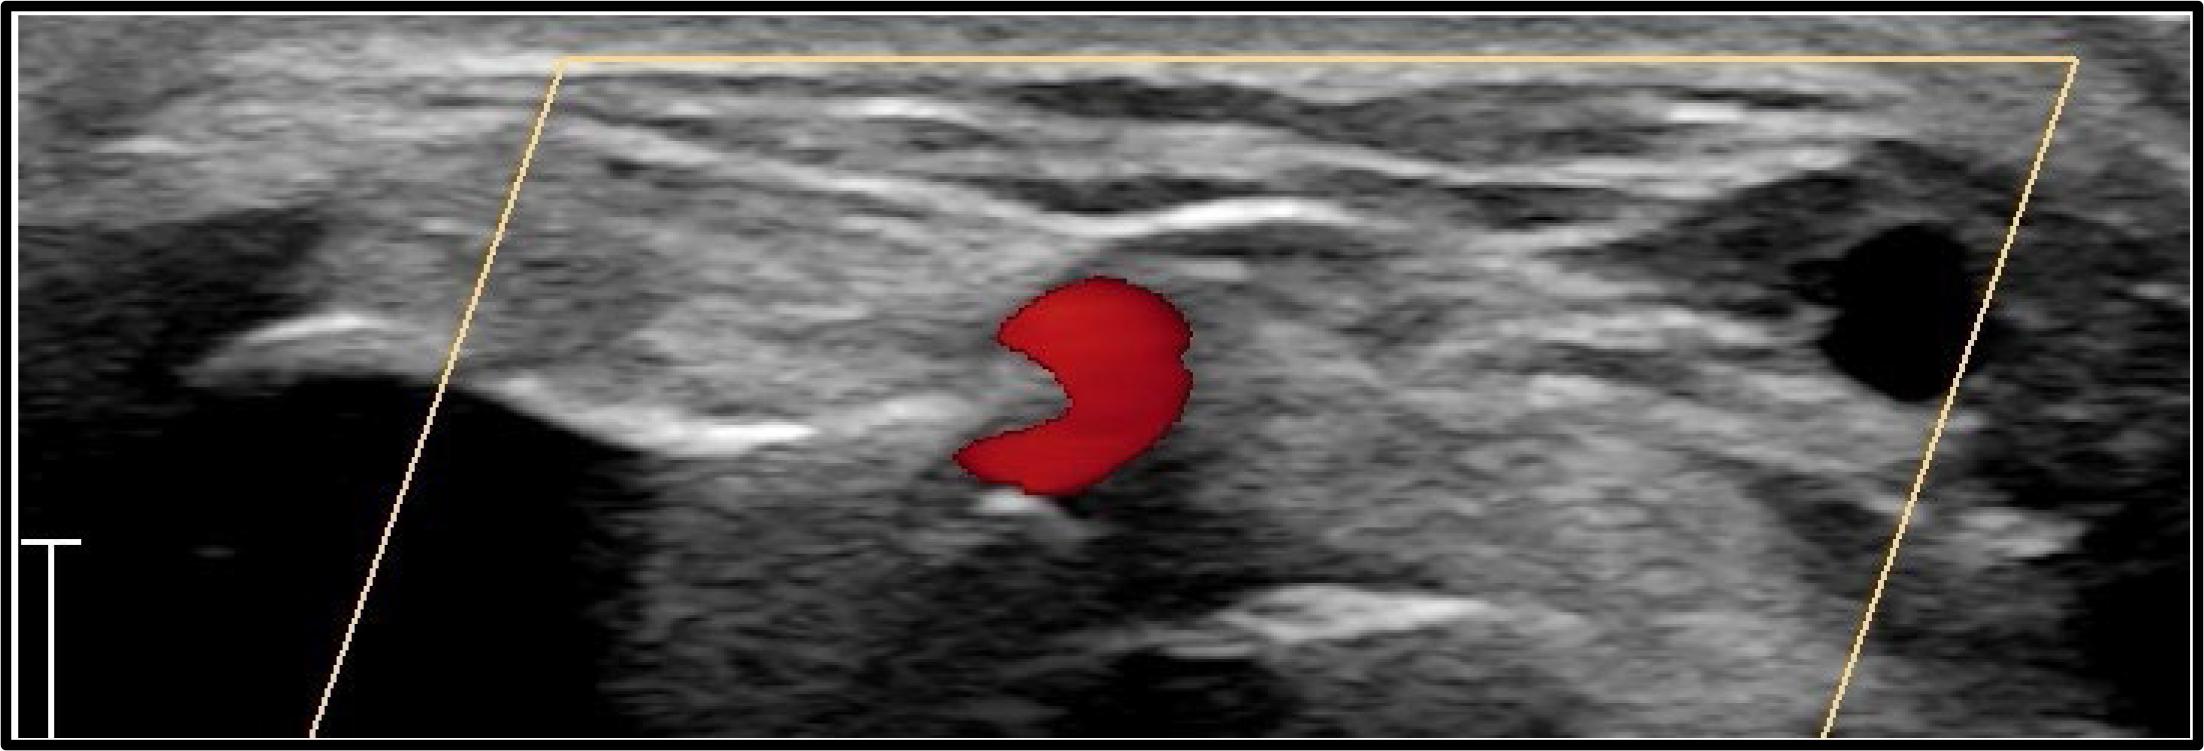

Ultrasound makes it easy to identify the scaphoid floor, extensor pollicis longus, and extensor pollicis brevis, accurately locating the distal radial artery and the optimal puncture site in a non-angulated segment, thus avoiding multiple punctures (Figure 2). Additionally, ultrasound allows the operator to measure the arterial diameter, ensuring appropriate sizing for the planned or potentially needed intervention.

A detailed ultrasound (US) analysis of the surrounding structures is recommended to select the optimal puncture site for distal radial access (DRA). The ideal site should be chosen based on several factors. First, the distance between the skin and the artery should be minimized to ensure the most superficial trajectory possible, facilitating easy access. Additionally, the DRA should be positioned close to a bone structure to secure effective compression and facilitate anastomosis. It is crucial to screen the surrounding structures to avoid puncturing the cephalic vein, superficial branches of the radial nerve, and, most importantly, the extensor tendons. Lastly, evaluating the tortuosity of the artery and visualizing its curvilinear trajectory in the long axis can help select the most suitable puncture site (Figure 2).

In a hyperextended wrist position, the puncture site is identified on the proximal wrist fold, proximal to the pisiform bone (Figure 2). Care should be taken to the risk of ulnar nerve injury. Using the precise location of the maximal pulse prominence or ultrasound guidance, the puncture is performed using the Seldinger technique using a 21-gauge needle, through which a 0.021-inch soft wire is passed. The sheath of the desired size (up to 7F) is then inserted over the wire. Certain degrees of possible vasospasm can be prevented using routine vasodilators such as intraarterial nitroglycerin or verapamil, while heparin administration reduces the occurrence of arterial thrombosis (2500-5000 IU). As a final step, after the termination of the procedure, the sheath is removed, and local hemostasis is obtained using either TR-band (Terumo, Tokyo, Japan) or other improvised basic compression devices. Given the deep-seated position of the UA, if a TR-band device is used for hemostasis, a higher inflation pressure is needed compared to radial artery hemostasis.47